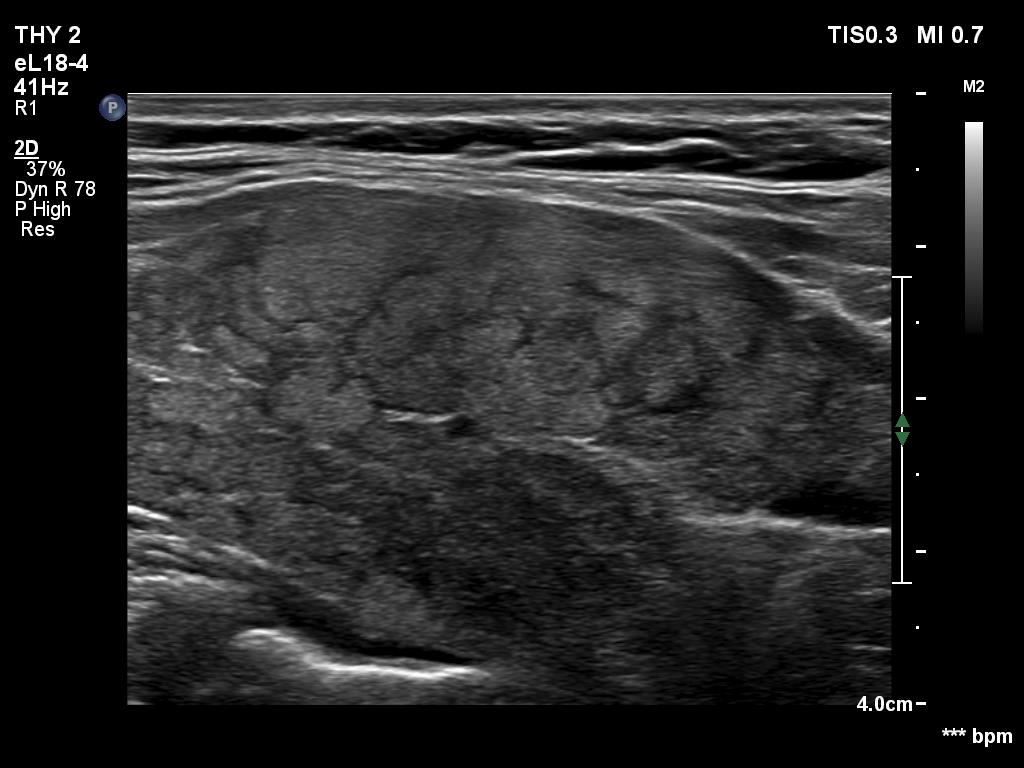

First examination (first row of images):

Ultrasonography. The thyroid was composed of hypoechoic and isoechoic islets divided by hypoechoic bands. The presentation corresponded to micronodular pattern.Suggestion: daily 75 microgram levothyroxine. The is 3 months, ultrasound in three years.